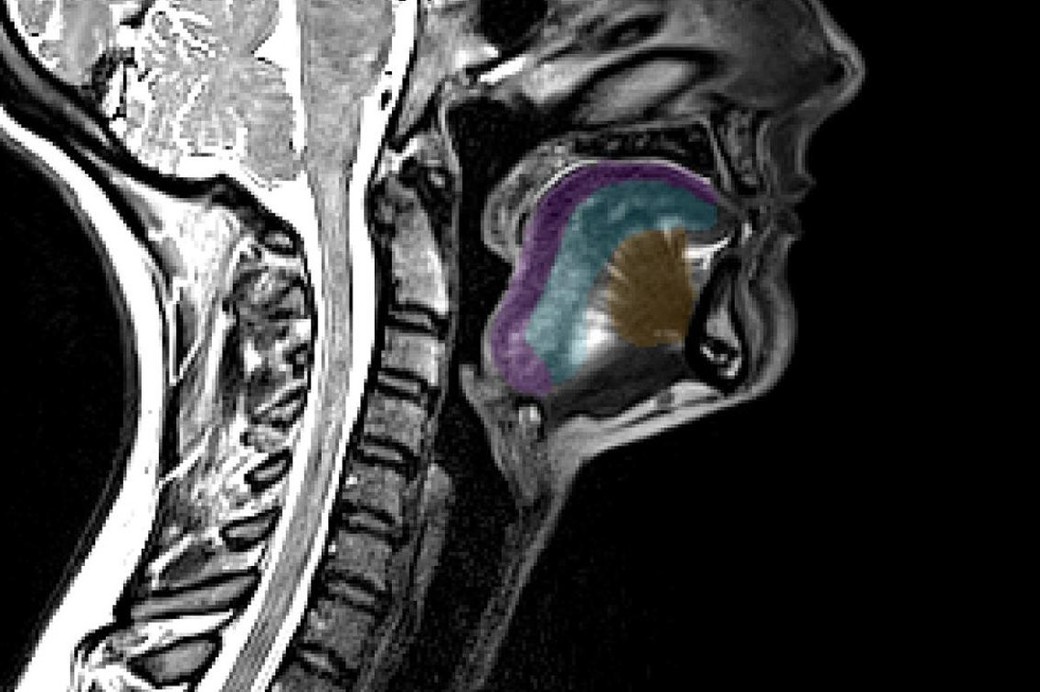

Scanările RMN standard ale limbii unei persoane ar putea ajuta la depistarea timpurie şi la monitorizarea evoluţiei sclerozei laterale amiotrofice (SLA). Credit: Universitatea din Queensland (UQ), 23 octombrie 2025

Foto articol: O scanare RMN care arată limba, în culori. Credit: Universitatea din Queensland, 23 octombrie 2025.

Dr. Thomas Shaw, care a condus cercetările, a explicat că limba umană este formată din opt muşchi interconectaţi, fiecare cu un rol precis în vorbire, masticaţie şi înghiţire. În cazul pacienţilor cu SLA, aceşti muşchi se atrofiază treptat, la fel ca multe alte grupe musculare afectate de boală. Detectarea timpurie a acestor modificări ar putea ajuta pacienţii să aibă acces mai rapid la tratamente experimentale şi la studiile clinice.

Echipa sa a analizat peste 200 de astfel de imagini, inclusiv de la persoane diagnosticate cu SLA, folosind metode avansate de imagistică asistată de inteligenţă artificială (AI) pentru a măsura cu precizie volumul şi forma muşchilor limbii.